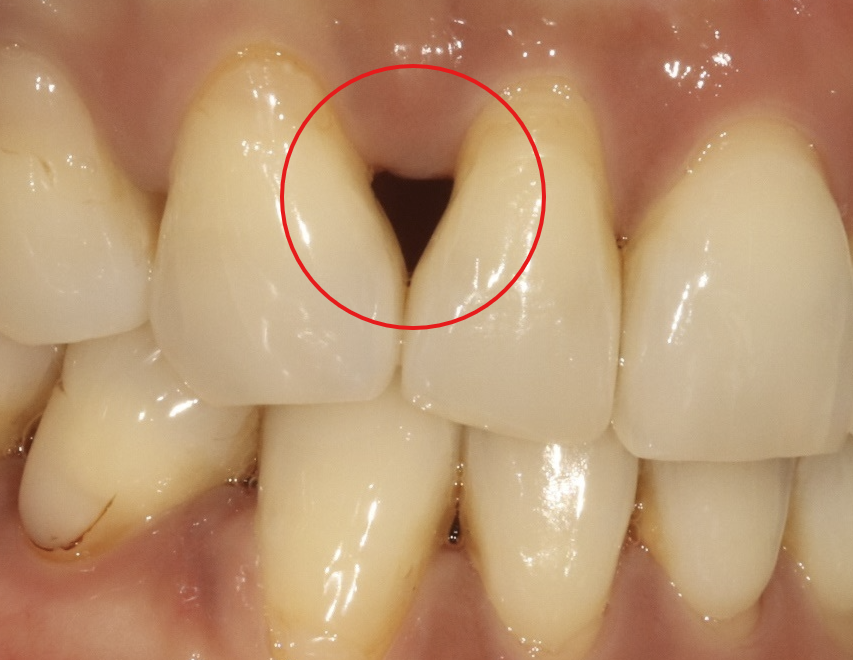

처음에는 크게 눈에 띄지 않았지만, 시간이 지날수록 상악 앞니 두 개 사이에 검은 삼각형 모양의 공간, 즉 '블랙트라이앵글'이 점점 커졌습니다.

블랙트라이앵글(Black Triangle)은 치아 사이 잇몸이 내려가면서 생기는 삼각형 모양의 빈 공간을 말합니다. 주로 다음과 같은 원인으로 발생합니다

교정 후 생긴 블랙트라이앵글, 바이오클리어로 자연스럽게 해결 - 이미지 2